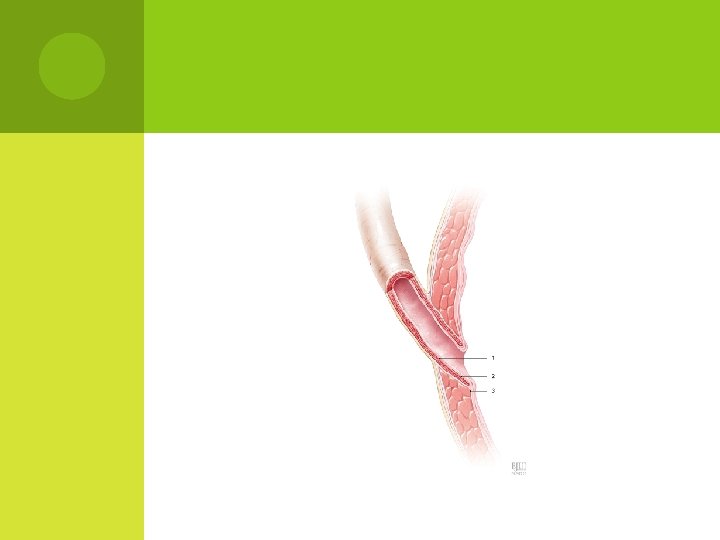

BLADDER SUBMUCOSAL TUNNEL cement of the ureteral orifice

Diagram of the bladder submucosal tunnel t submucosal tunnel Cooper, C. S. (2009) Diagnosis and management of vesicoureteral reflux in children Nat. Rev. Urol. doi: 10. 1038/nrurol. 2009. 150